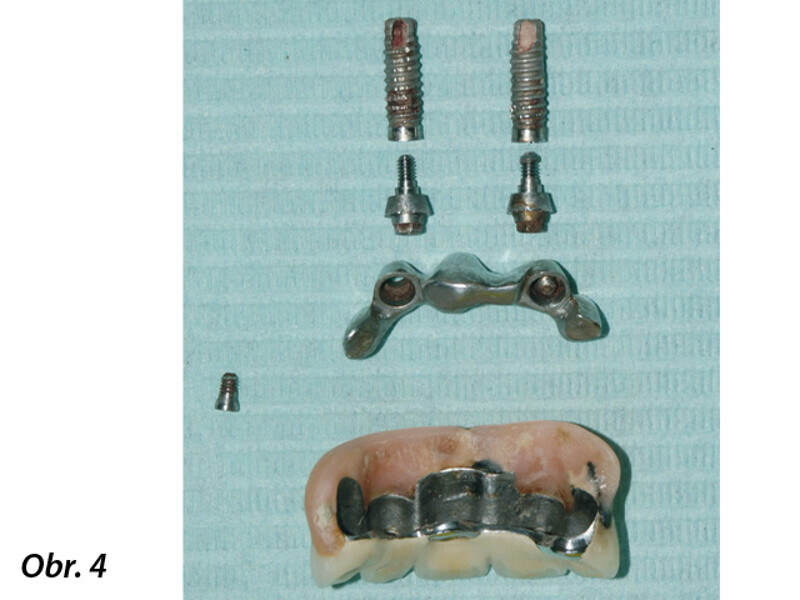

Opětovné implantologické ošetření